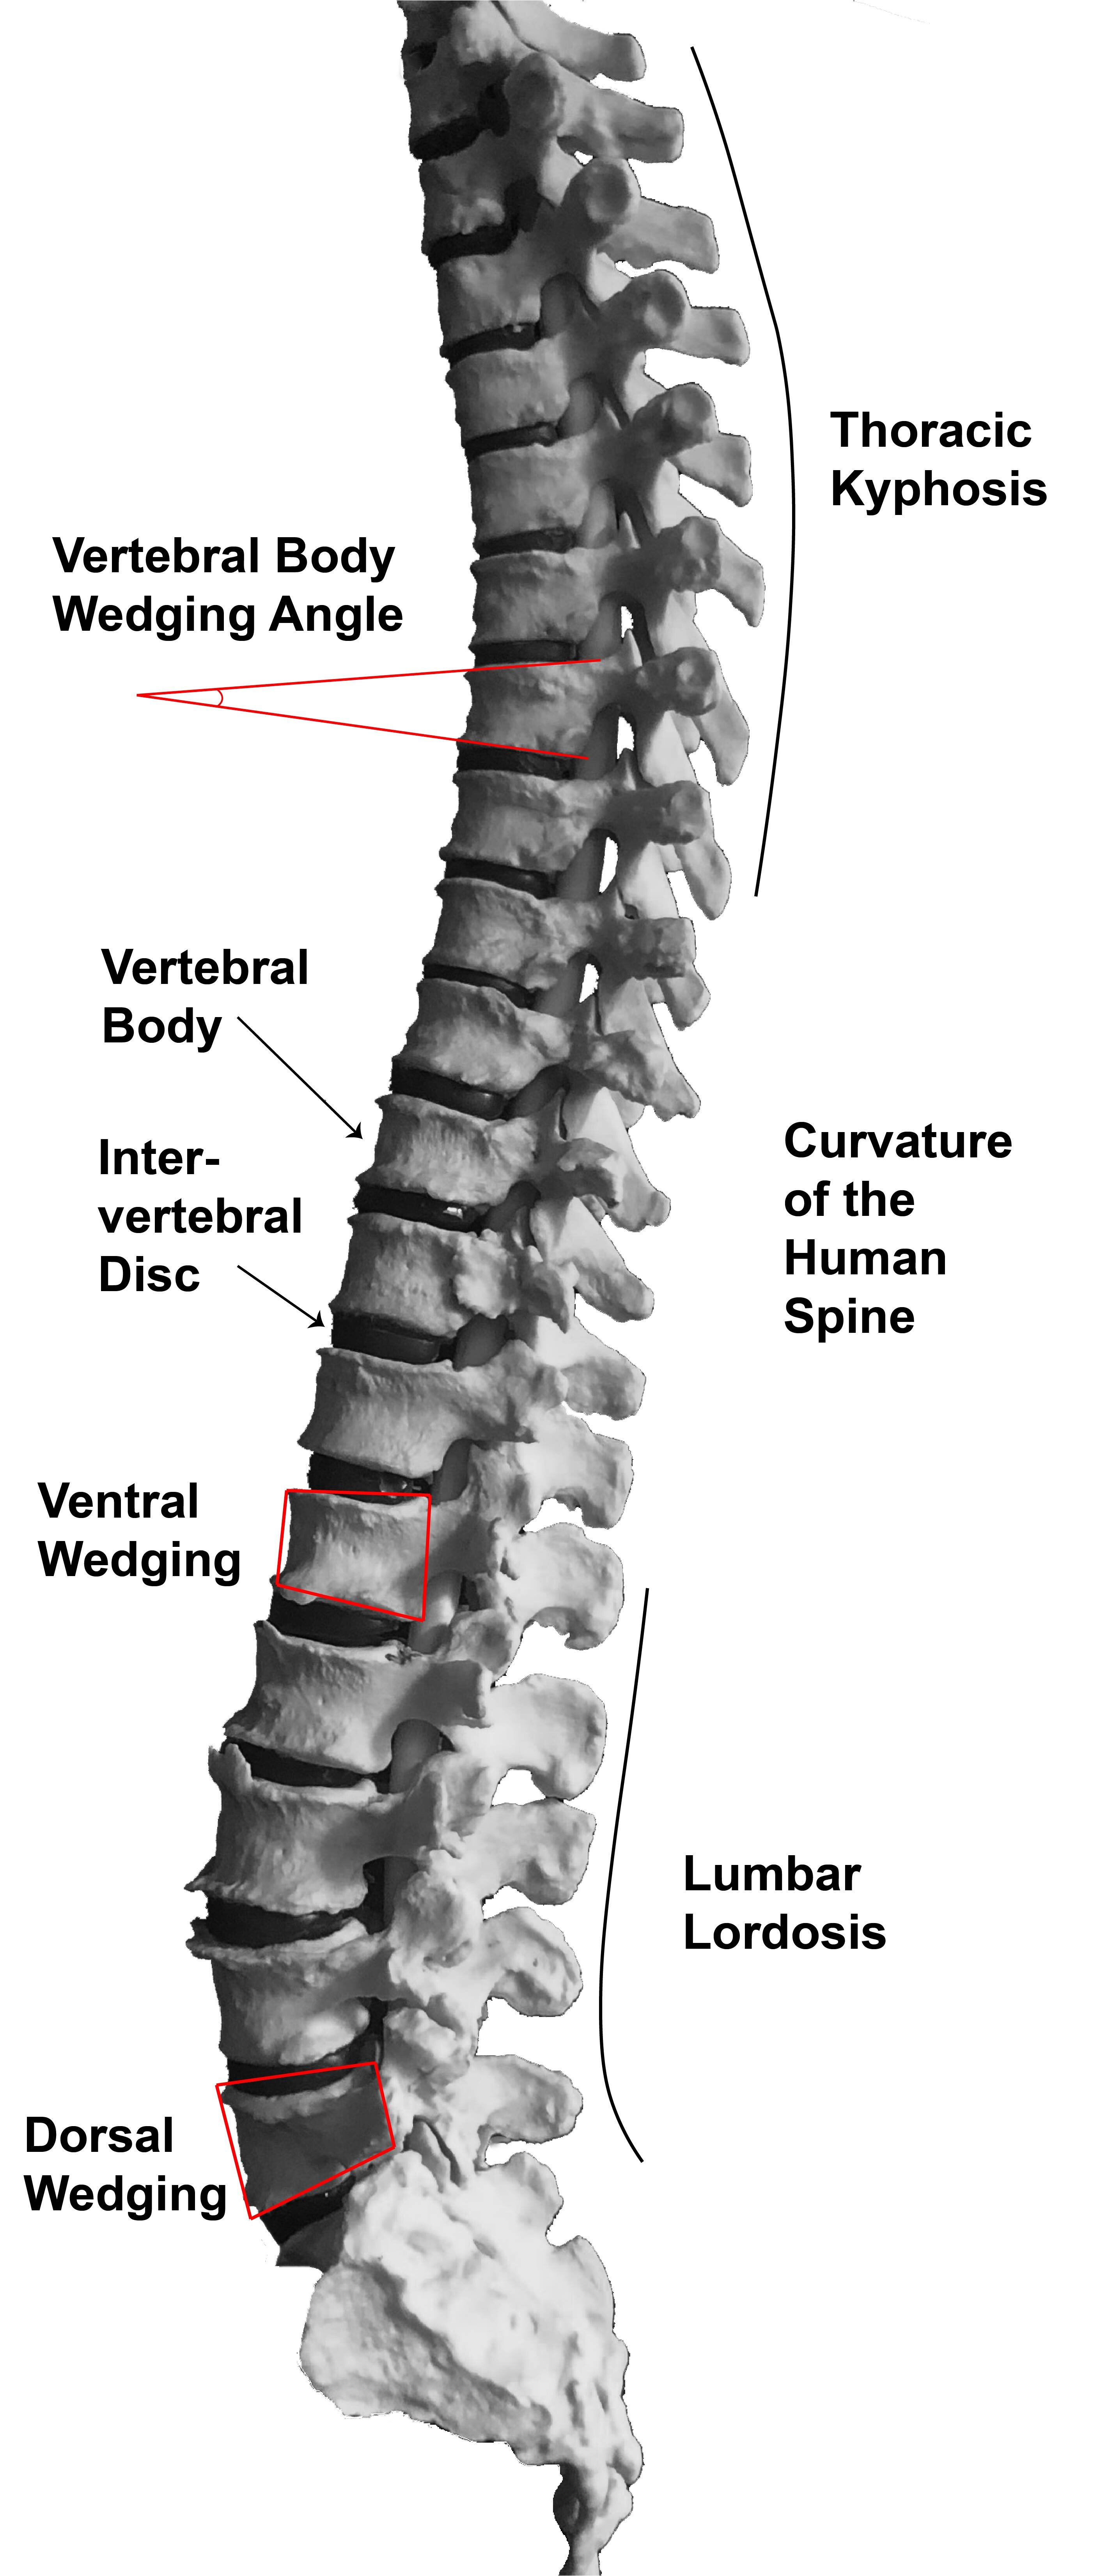

What Explains Our Lower Back Pain Anthropologists Turn To Neandertals

https://scx2.b-cdn.net/gfx/news/hires/2022/what-explains-our-lowe.jpg